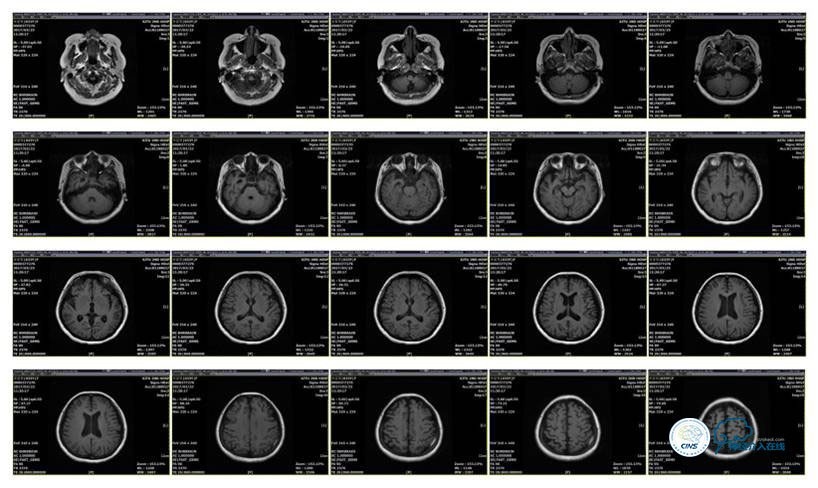

MRI T1

MRI T2

病史:患者于1年余前,因头部外伤在外院行头颅CT提示:未见异常。约3月后患者出现头痛、发作性意识丧失,在当地医院行头颅CT及MRI提示:未见明显异常。诊断为外伤性癫痫,予以对症治疗,未见明显好转。6月余前,无明显诱因出现鼻腔漏液,予以保守治疗,此后鼻腔间断漏液,漏液后头痛缓解。13天前因高热、恶心、呕吐在外院诊断为颅内感染(肺炎链球菌),予以抗炎等对症治疗2周后鼻漏停止,体温正常,CSF常规、生化正常,但头痛仍未缓解,转入我院神经内科治疗。反复腰穿颅内压450-500mmH2O左右,脑脊液常规及生化均正常。颅脑CT及MRI、MRV提示:左侧顶叶硬膜下血肿,鼻窦炎、乳突炎、左侧横窦、乙状窦闭塞、右侧横窦、乙状窦狭窄。予以华法林抗凝治疗2周,维持INR2-3,患者头痛仍无明显缓解,颅内压无下降,转入我科。

诊断:1、右侧横窦、乙状窦狭窄;2、硬膜下血肿(左侧顶);3、继发性癫痫;4、脑脊液鼻漏;5、颅内感染;6、乳突炎;7、鼻窦炎。

病理过程推理:首先是乳突炎—诱发左侧横窦乙状窦血栓最终闭塞,右侧横窦乙状窦狭窄—导致颅内高压,造成头痛及癫痫—持续颅内高压—皮层静脉回流受阻导致自发性硬膜下血肿及自发性脑脊液鼻漏—颅内感染。